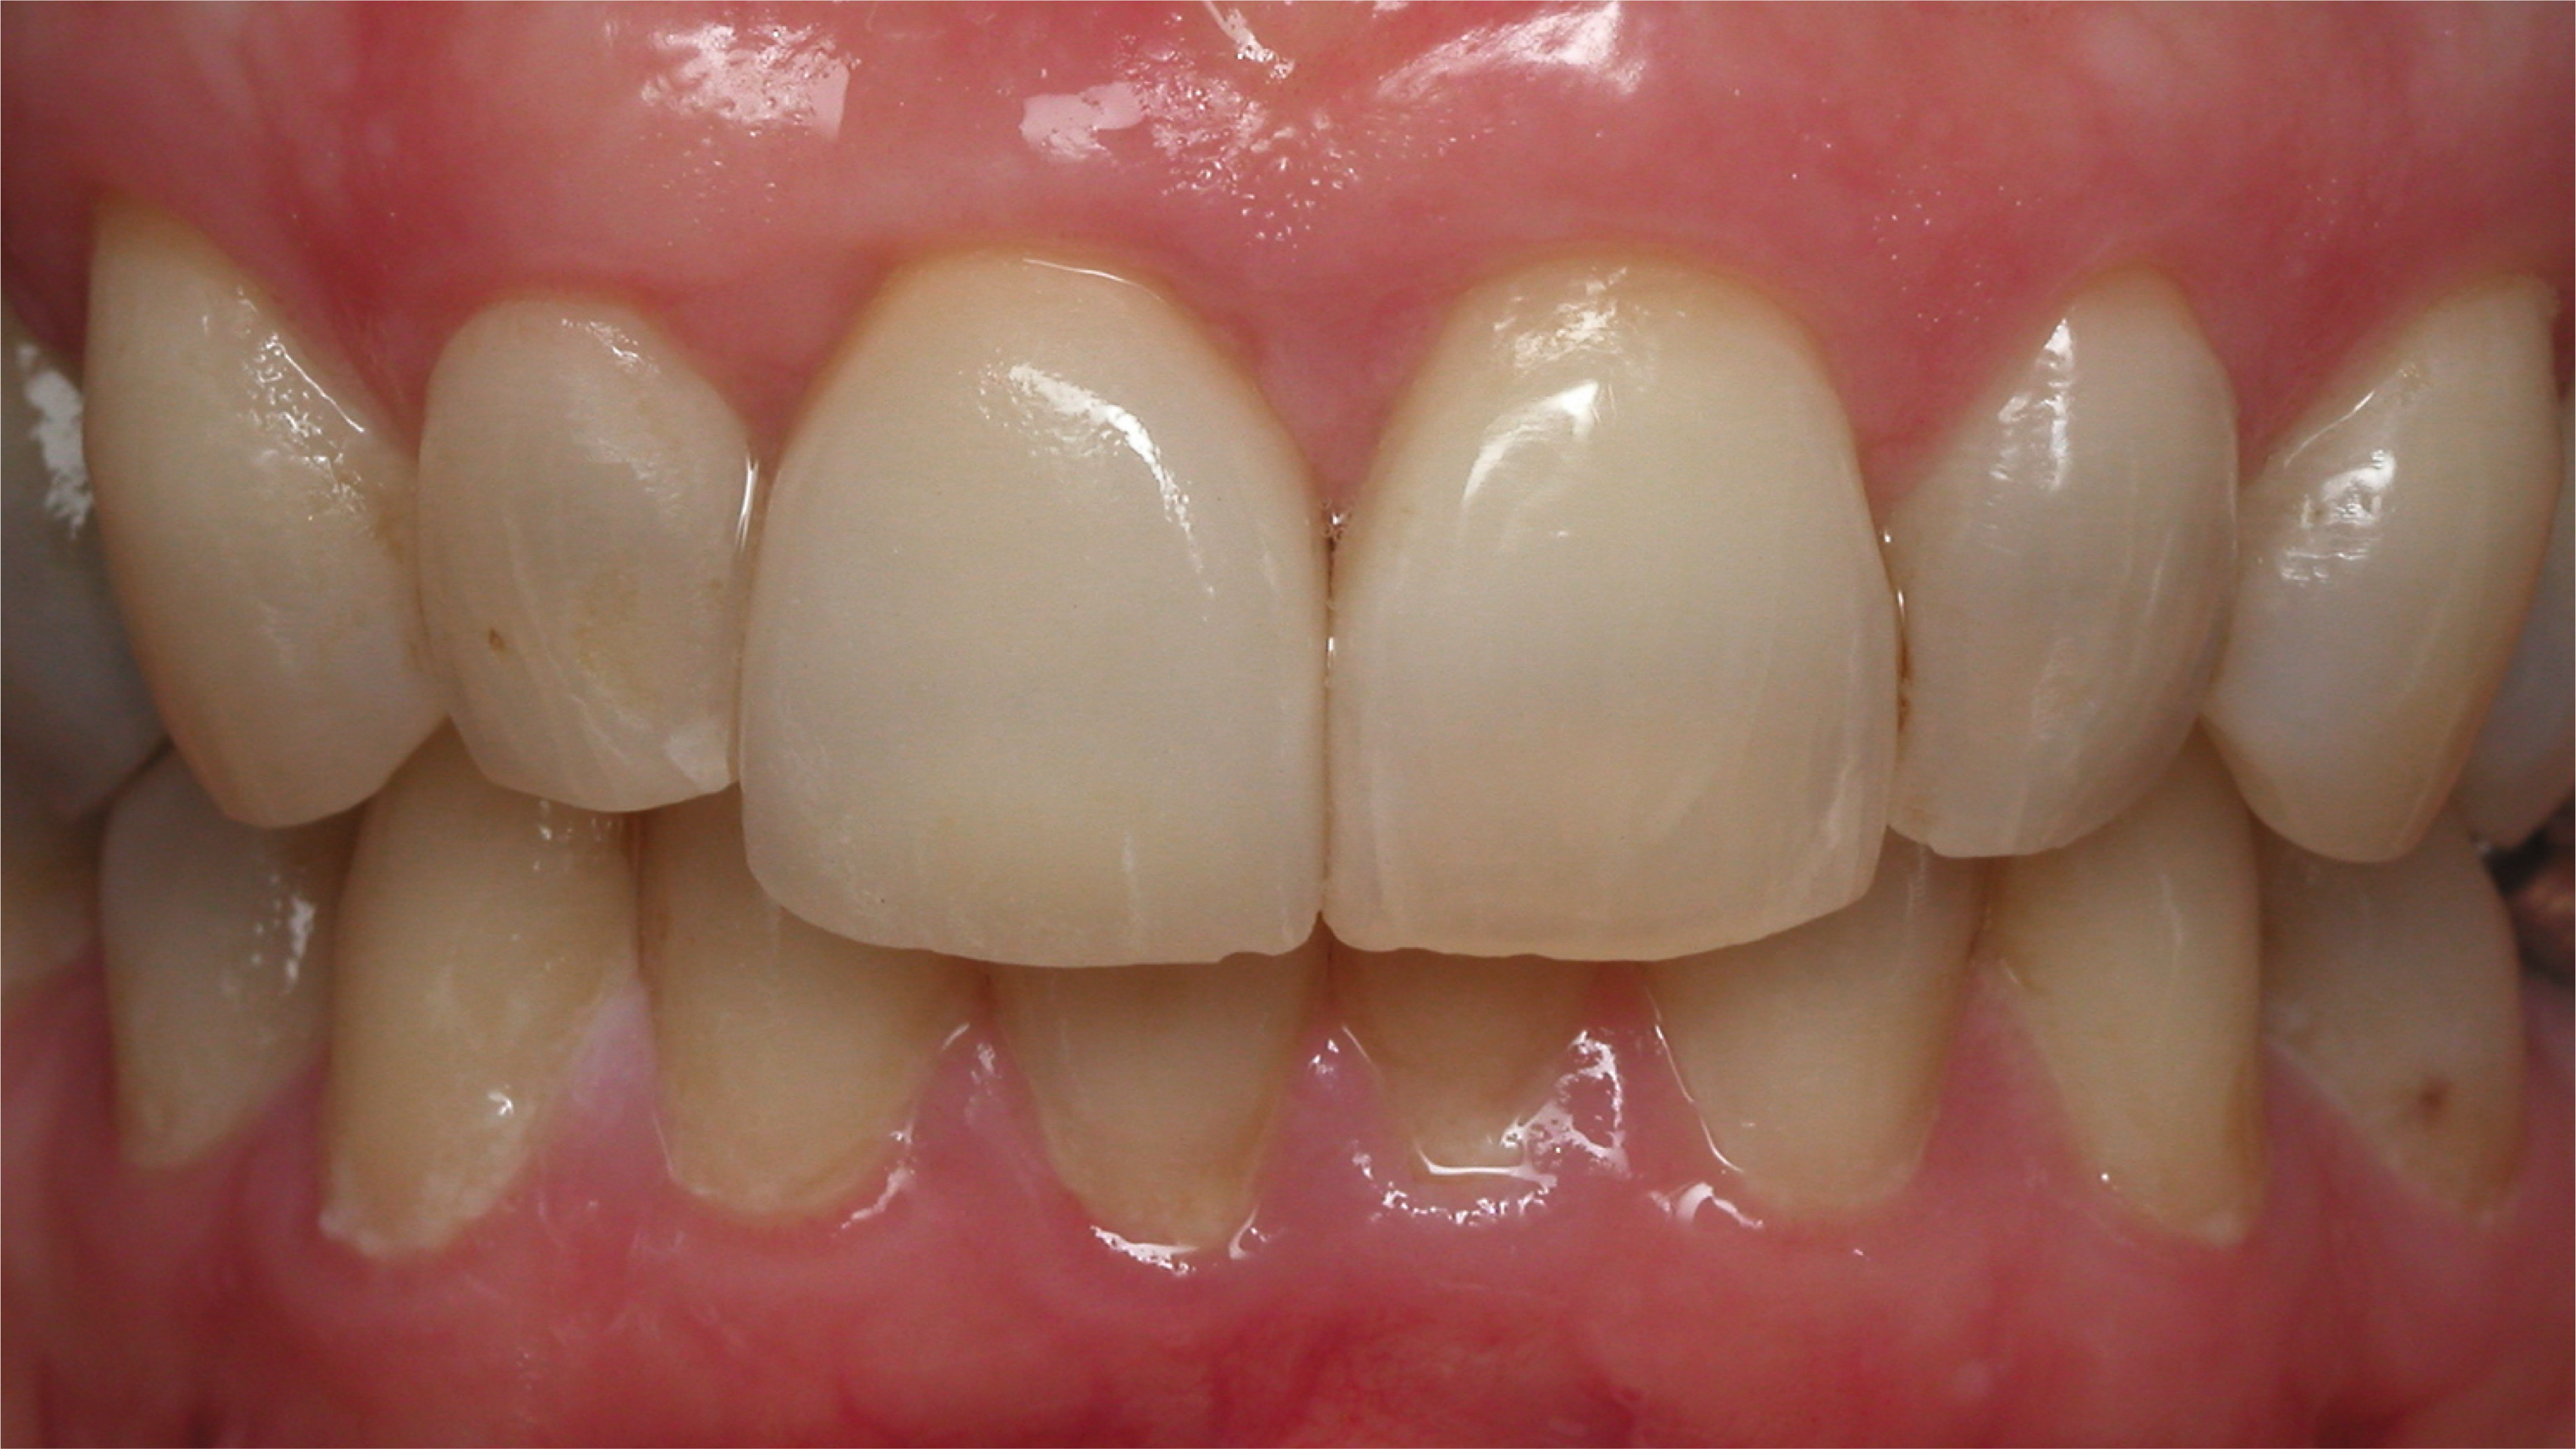

An example illustrating the manner in which these factors are considered in case selection, implant placement, and implant restoration is the case of a female patient who presented with a missing central incisor, tooth No. 8 (Figure 1 and Figure 2). While this example presents an ideal situation for a single implant-supported restoration, analysis is required to determine the appropriate implant width and length, presence of adequate bone, quality and quantity, soft-tissue health, abutment type (ie, custom or stock), and restoration type (ie, cement- or screw-retained).

Fig 1. A female patient presented missing tooth No. 8, which would be replaced with a single implant restoration.

Figure 1